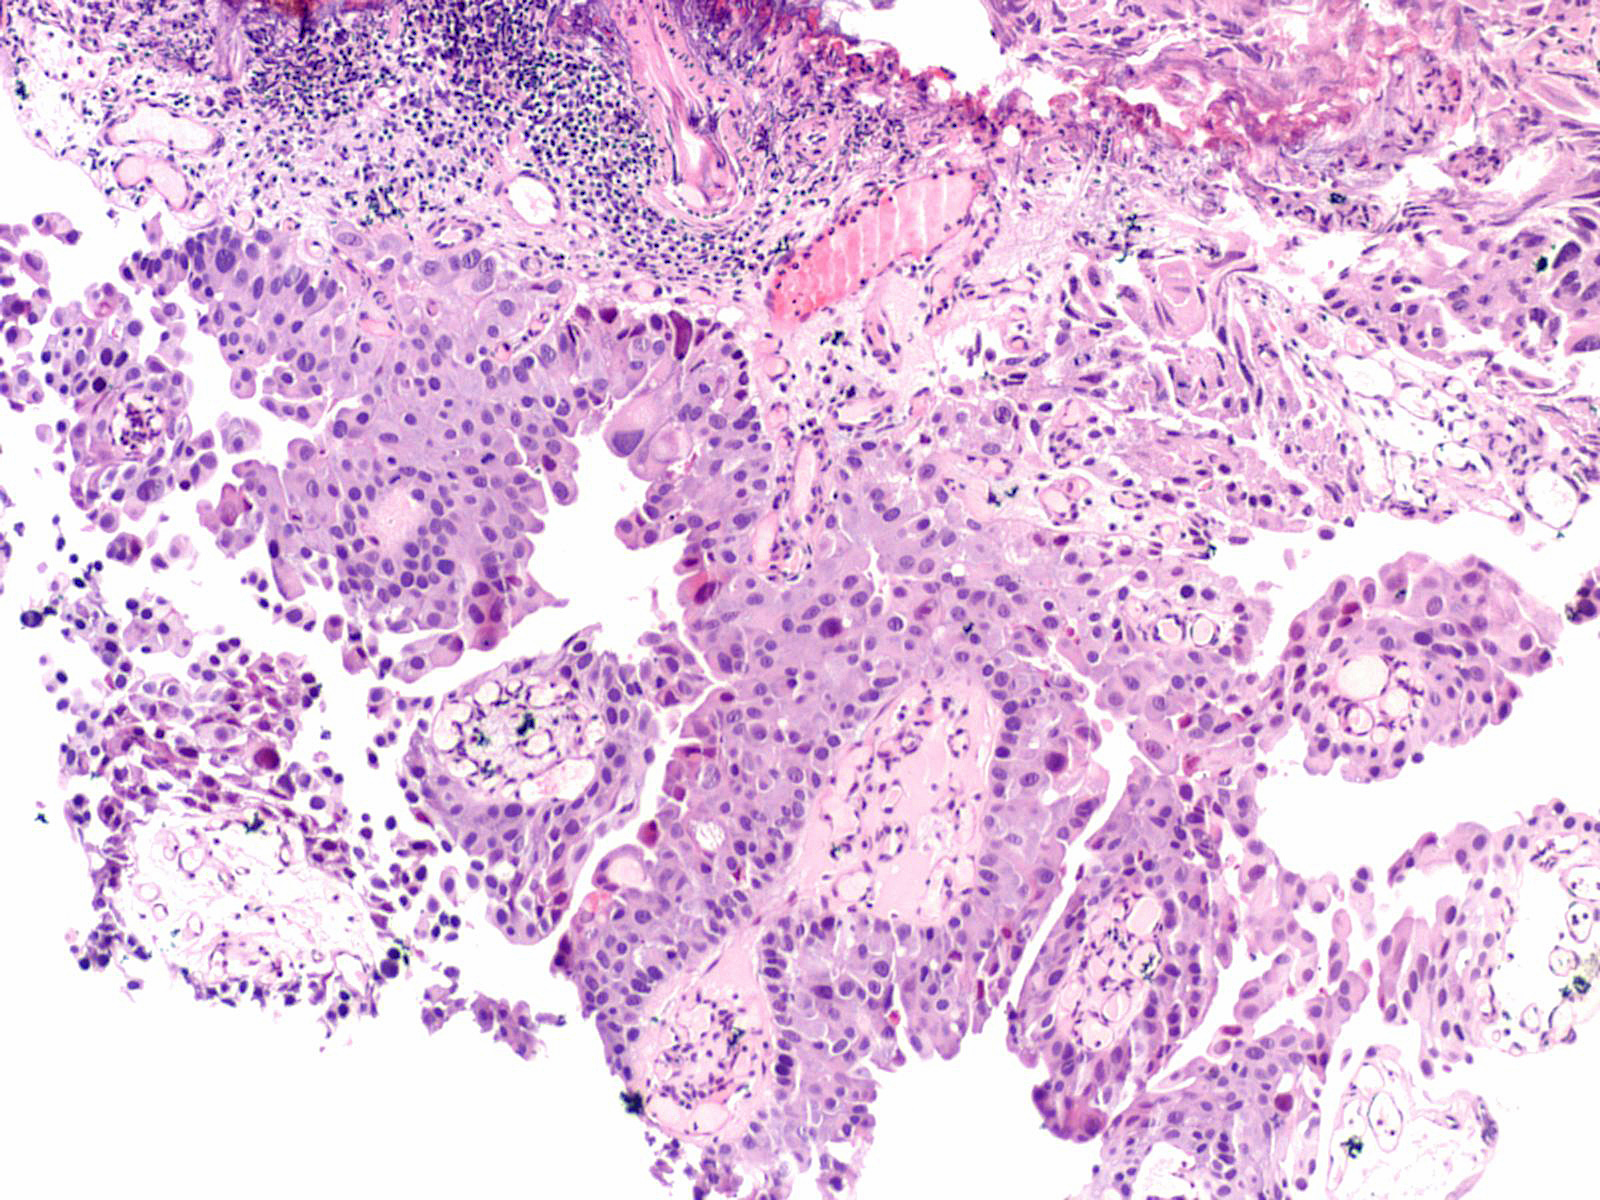

Consensus grade: High-grade papillary urothelial carcinoma (HG-PUC)

Lesion shows marked variation in nuclear size, shape and chromatin. Architecturally, cells appear loosely cohesive and the epithelium is disorganized. Mitotic figures are seen.